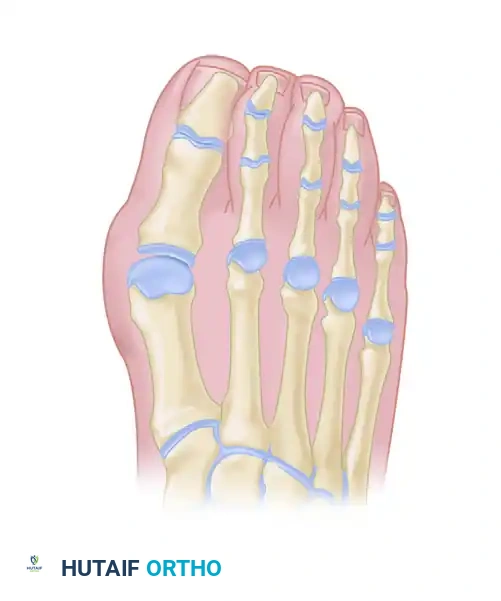

The classic "rheumatoid foot" presents with severe hallux valgus, dorsal subluxation or frank dislocation of the lesser metatarsophalangeal (MTP) joints, claw toes, hammer toes, and the formation of painful adventitial bursae. As the proximal phalanges subluxate dorsally, the plantar metatarsal fat pad is drawn distally, leaving the prominent metatarsal heads directly exposed to plantar pressure, leading to intractable plantar keratoses and ulceration.

Forefoot arthroplasty is directed primarily at the severe metatarsophalangeal joint deformities. The overarching goals are to relieve pain, correct deformity, improve cosmesis, enhance ambulatory function, and allow the patient to wear a reasonable variety of footwear.

Regardless of the specific surgical approach (plantar vs. dorsal incisions), adequate bony resection is mandatory. The phalanges must be allowed to realign loosely with the metatarsal remnants without any soft tissue tension. Insufficient relaxation of the soft tissues around the MTP joints due to inadequate bone resection will severely compromise the result, leading to recurrent dorsal subluxation and stiffness.

The Metatarsal Cascade

When performing a resection arthroplasty, the surgeon must carefully contour the remaining metatarsal necks. Unequal lengths of the metatarsal remnants, or metatarsals that do not cascade in a gentle, parabolic curve from metatarsals two through five, will result in transfer metatarsalgia and a compromised outcome. Furthermore, any bony fragments left in the forefoot weight-bearing pad will act as symptomatic pebbles, causing severe localized pain.

Surgical Options for the Lesser Rays

Resection of all five metatarsal heads, or fusion of the first MTP joint combined with resection of metatarsals 2 through 5, have both been shown to produce excellent results. All four of the lesser toes must be treated in the same manner, regardless of the varying severity of involvement of each individual ray. While there are rare exceptions where only one or two lesser metatarsal heads are removed, the patient must be warned that subsequent surgeries to remove the remaining heads are highly likely as the disease progresses.